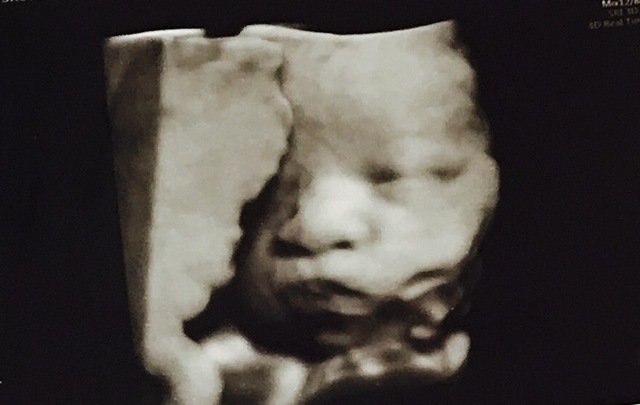

34週0日(34w0d・女の子)|smileai さん(26歳)

エコー写真撮影時のエピソード:

検診でなかなか顔を見せてくれることがなく、4Dでも顔がお腹に近すぎで見れなく、やっと顔がしっかり見れて嬉しかったのを覚えています。普通のエコーでもこんなにはっきり顔が見れて驚きました。口をもぐもぐしていてとても愛しかったです。私の体調はすこぶる良く、散歩に旦那も付き合ってくれ妊婦生活を楽しんでいました。体重が増えすぎるのも怖かったので外食は控え、家で食べることを心がけました。そのおかげもあってか順調でした。